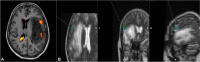

Background The extent of resection for brain tumors is a critical factor in determining the oncologic outcome for a patient. However, a balance between preservation of neurological function and maximal resection is essential for true benefit. Functional magnetic resonance imaging (fMRI) is one of the approaches that augments the neurosurgeon's ability to attain maximal safe resection by providing preoperative mapping. It may not be possible to perform awake craniotomy with intraoperative localization by direct cortical stimulation in all patients, such as children and those with neurocognitive impairment. Task-based fMRI may have limited value in these cases due to low patient cooperability. Methods In this article we present in a case-based format, the various clinical scenarios where resting state fMRI (rs-fMRI) can be helpful in guiding neurosurgical resection. rs-fMRI of the patients has been acquired on Philips 1.5 T system. Seed voxel method has been used for processing and analysis. Conclusion rs-fMRI does not require active patient cooperation to generate useful information and thus can be a promising tool in patients unable to cooperate for task-based studies.